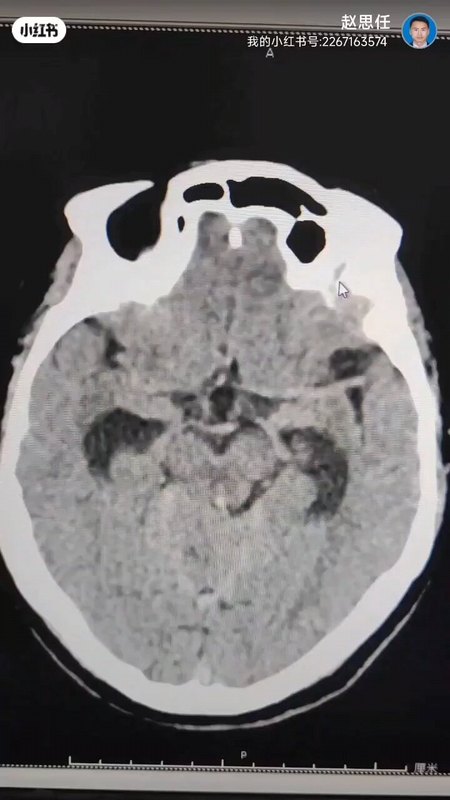

脑出血来势汹汹极恐怖,重视并发复发随访很必要

脑血肿康复案

脑出血妈妈的康复之路 千里奔袭的救命之旅,源于信任、出于责任;虽充满挑战,却也满怀希望

脑出血后重度昏迷3个月了,还要不要坚持?